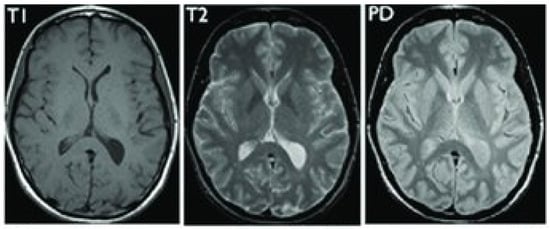

5. Database and Dataset

5.1. DataBase Collection